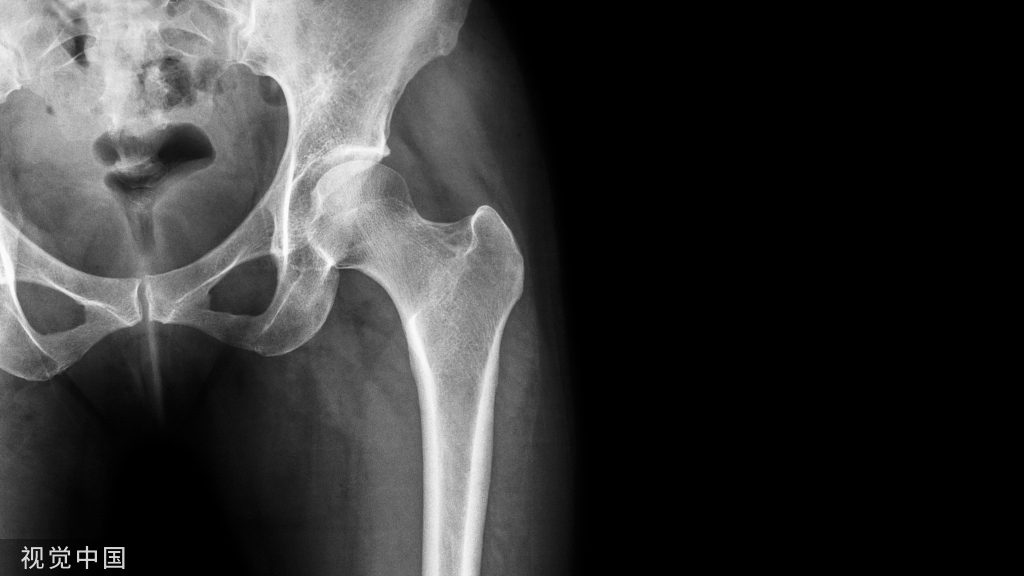

单纯的压缩骨折

对于单纯的压缩骨折来说,应用AO经典的撑开复位技术就可以达到复位